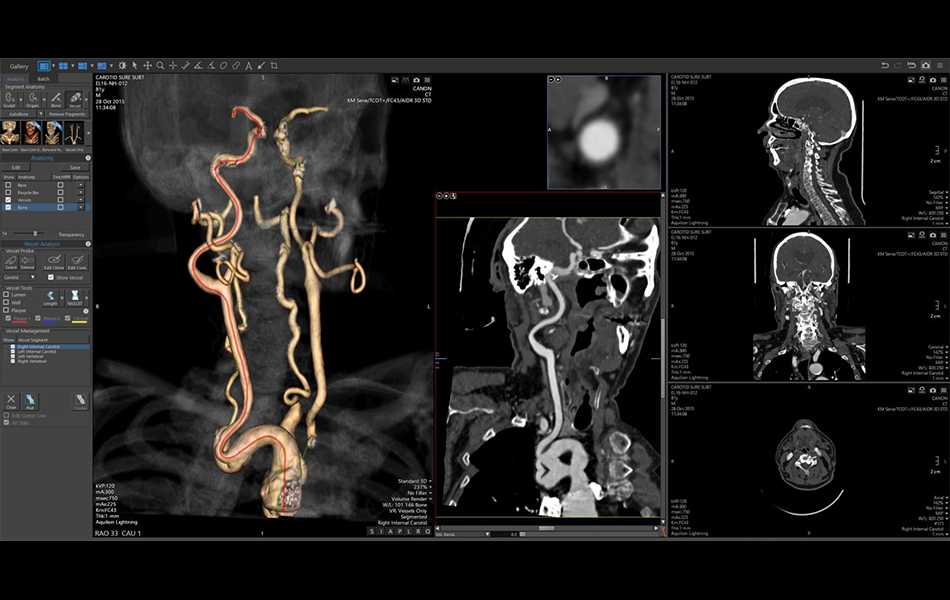

CT Carotid Auto Vessel (7.15.8)

CT Carotid Auto Vessel enables a simplified workflow with the automatic initialization of internal carotids and vertebral artery vessels.